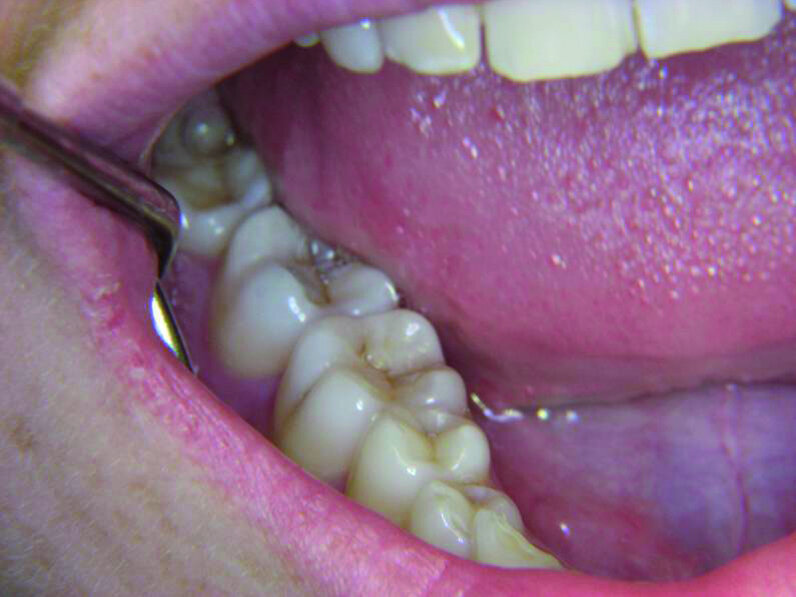

Les premières molaires (Fig. 7) sont étroitement associées au désir d’être reconnu dans la société comme dans la famille. L’atteinte des idéaux pour améliorer notre position dans la société est liée à la première molaire supérieure droite ainsi qu’à la première molaire inférieure droite, et ces dents reflètent notre vie professionnelle et notre réussite à cet égard. La patiente présentée à la figure 8 avait dû renoncer à sa passion professionnelle en raison de circonstances familiales qui l’avaient contrainte à déménager et demeurer chez elle. Après un traitement endodontique de la seconde prémolaire supérieure droite et de la première molaire supérieure droite (dents 15 et 16), elle a présenté une importante lésion périapicale de la dent 16 quelques années plus tard (Fig. 9). Elle n’avait probablement pas encore accepté sa nouvelle situation.